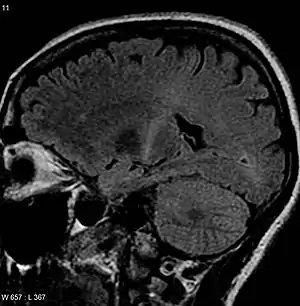

A esclerose lateral amiotrófica (ELA), também conhecida como doença do neurônio motor e doença de Lou Gehrig, é uma doença que causa a morte dos neurônios de controle dos músculos voluntários.[4][10] Alguns também usam o termo doença do neurônio motor para um grupo de condições de que ELA é o mais comum. ELA é caracterizada por rigidez muscular, espasmos musculares, e, gradualmente, aumento da fraqueza, devido aos músculos diminuindo de tamanho. Isto resulta em dificuldade de fala, deglutição, e, por fim, da respiração.[2][3]